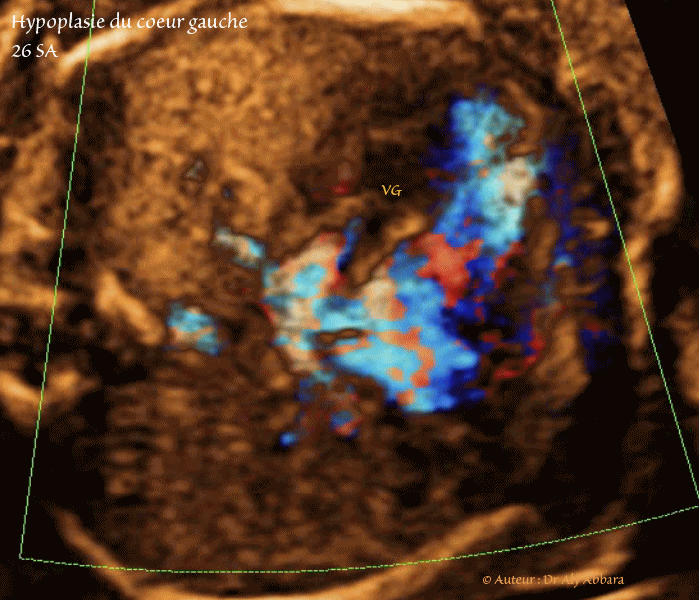

Coupe thoracique axiale

- Images échographiques avec étude du Doppler couleur (Dynamic-Flow) animées montrant des multiples signes échographiques liés à la présence d'une hypoplasie du cœur gauche à 26 SA :

Une atrésie mitrale se manifestant par une sténose et fibrose sévère de la valve mitrale qui parait immobile, sans mouvements de fermeture et d'ouverture ce qui ne laisse passer qu'un très faible flux sanguin de l'oreillette gauche au ventricule gauche (ventricule muet à l'étude des flux sanguin par Doppler type Dynamic-Flow).

- Hypoplasie de l’oreillette gauche : cette oreillette reçoit bien le flux sanguin de retour veineux pulmonaire.

Valvulus de Vieusens battant dans l’oreillette droite en raison de l'augmentation de la pression dans l'oreillette gauche avec inversion du flux sanguin entre les deux oreillettes à travers le foramen ovale : oreillette gauche > l'oreillette droite (dans un cœur foetal normal, c'est l'inverse : oreillette droite > oreillette gauche).

Donc l'oreillette gauche ne se vide pas dans le ventricule gauche ; elle se vide dans l'oreillette droite.

- Hypoplasie sévère du ventricule gauche : il s'agit d'un ventricule globuleux ; ses parois sont hyper-échogènes par un phénomène de fibro-élastose touchant l'endocarde.

- Hypoplasie de l'aorte ascendante et de crosse de l'aorte (aorte filiforme) : visible sur la coupe des trois vaisseaux et de trachée, puis sur la coupe sagittale de crosse de l'aorte, cette crosse suit un trajet irrégulier et tortueux.

Le flux sanguin repéré dans l'aorte serait rétrograde, venant du canal artériel via l'isthme aortique.